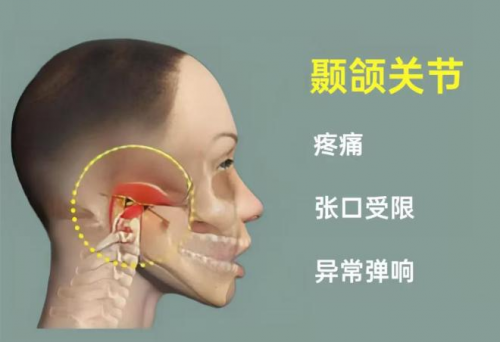

娄卫华教授提醒,如果耳部出现肿物、听力下降或耳鸣现象,务必及时前往正规医院接受检查。早期颞骨病变虽然症状轻微,但若拖延治疗可能会对听力及面部神经造成不可逆的影响。尽早诊治不仅能够降低治疗难度,还能帮助患者更快恢复正常生活。